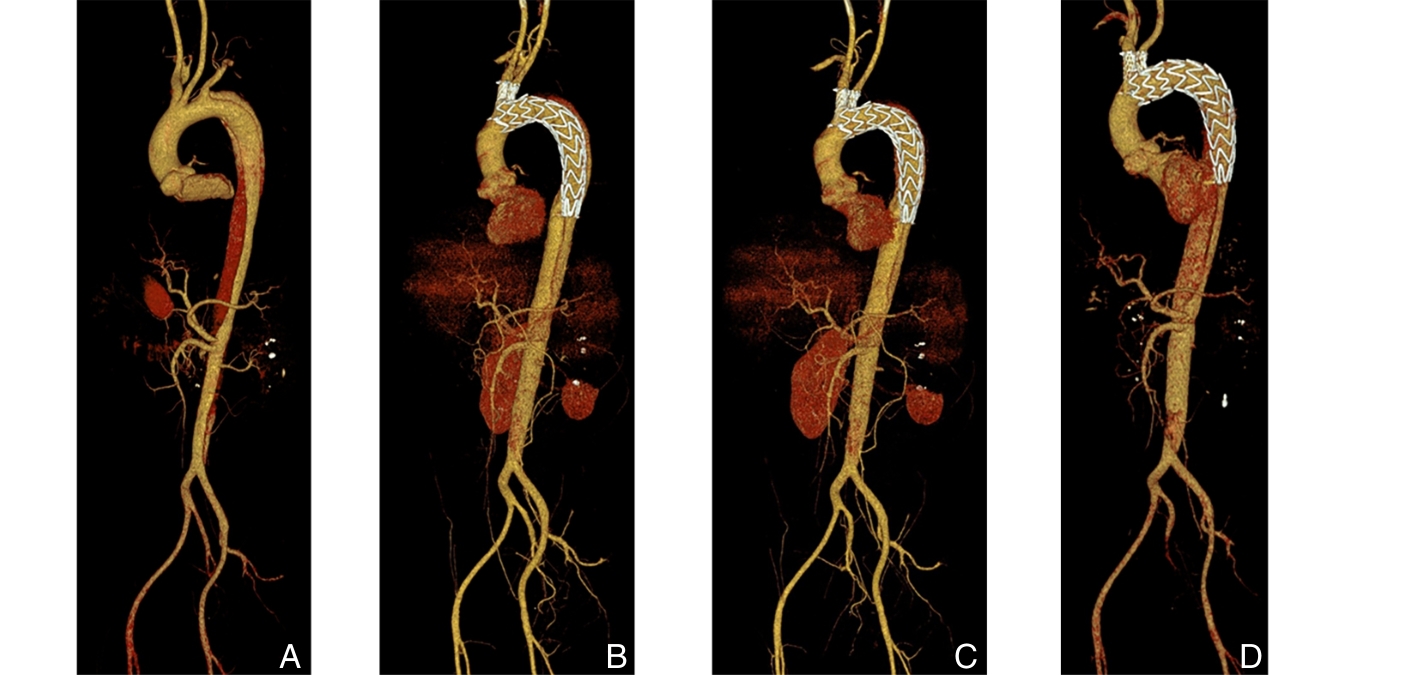

2025, 34(12):2577-2585. doi: 10.7659/j.issn.1005-6947.250429

摘要:背景与目的 胸主动脉腔内修复术(TEVAR)已成为治疗胸主动脉疾病的重要微创手段,但在近端锚定区位于Z0区的复杂主动脉弓部病变中,如何同期重建弓上分支血管仍是技术难点。Castor分支型主动脉覆膜支架可实现左颈总动脉(LCCA)的一体化重建,但其在Z0区应用通常需联合其他技术重建无名动脉(IA)。本研究旨在初步评估Castor分支型支架重建LCCA联合IA烟囱支架技术在Z0区TEVAR中的技术可行性及短期疗效。方法 回顾性分析2024年2月—2024年6月在中南大学湘雅二医院接受Castor分支型主动脉覆膜支架重建LCCA联合IA烟囱支架技术行Z0区TEVAR的主动脉疾病患者资料。收集并分析患者围手术期临床特征、手术相关参数及随访结果,主要观察指标包括技术成功率、围手术期并发症发生情况及弓上分支血管通畅率。左锁骨下动脉(LSA)是否同期重建依据术前影像学评估结果个体化决策。结果 共纳入6例患者,平均年龄51.5岁,男性5例。原发病包括主动脉夹层4例、主动脉弓部动脉瘤1例及穿透性主动脉溃疡1例。所有患者均成功完成手术,技术成功率为100%。其中3例同期行LSA血运重建。术后30 d内未发生死亡、脑卒中、截瘫、内漏、逆撕性A型主动脉夹层、支架移位及上肢缺血等严重并发症。中位随访13(11~15)个月,随访期间未出现主要不良心脑血管事件或支架相关并发症,影像学显示IA、LCCA及重建LSA通畅率均为100%。结论 在严格筛选的小样本患者中,Castor分支型主动脉覆膜支架重建LCCA联合IA烟囱支架技术用于Z0区TEVAR在技术上可行,且短期随访结果显示分支血管通畅率良好。但其安全性及远期疗效仍需通过更大样本量及长期随访研究进一步验证。